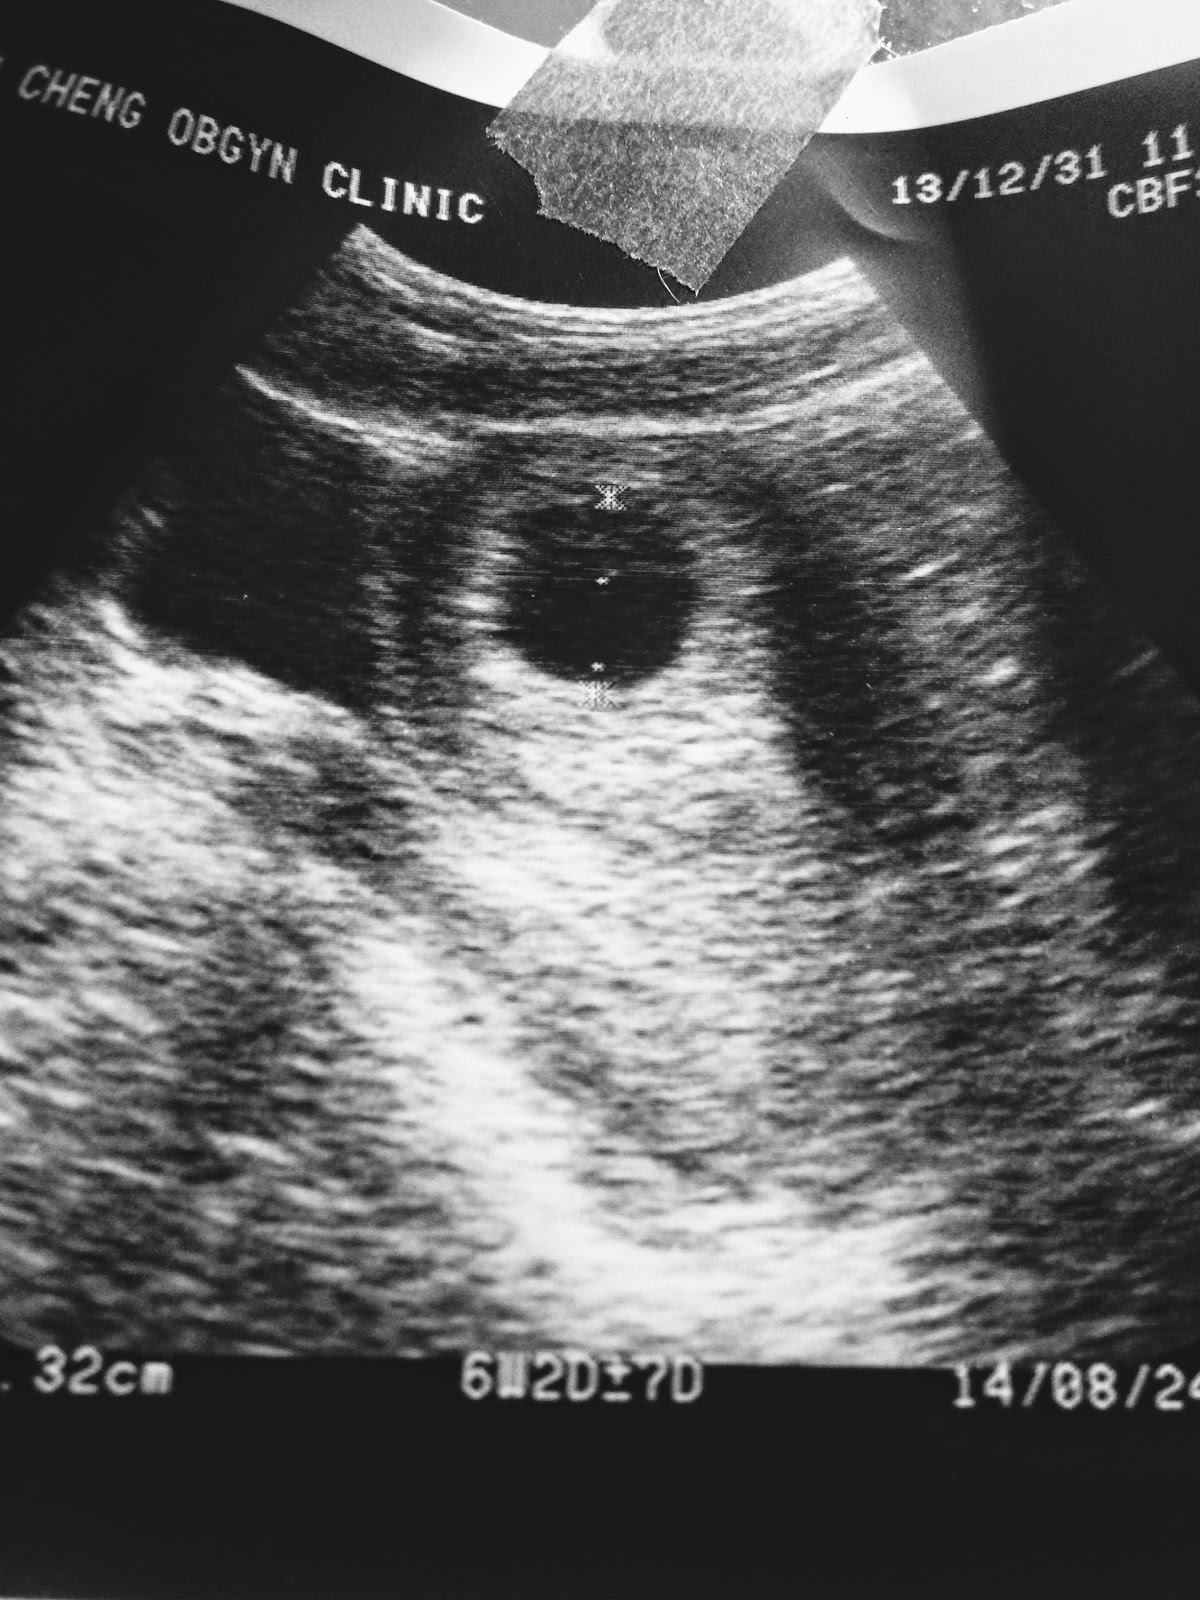

黃先生看著這張烏漆抹黑的照片:非常喜歡

當下我們沒有公佈這喜訊是礙於醫生說確定胚胎有著床成功,但是要等到八週後確定有心臟,沒有無腦水腦狀況才是真正有寶寶,這期間會有一些突發狀況,所以那時候就沒有跟大家分享這喜訊!!

黃先生每次都非常認真地聽醫生解釋很難看懂的超音波

5.設備雖不如一些大醫院和新診所,但是薑是老的辣!看超音波的功力超強~很多知名醫院和醫生看不出來的,他都可以發現到!

大小姐在那裡產檢到第四個月,他幫我轉診到彰化基督教醫院,婦產科主任許貴程醫生!